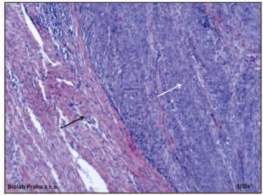

V definitivním preparátu patolog popsal makroskopicky dělohu velikosti 50 x 78 x 48 mm jejíž dutinu v celém rozsahu vyplňoval šedobělavý tumor tužší konzistence 31 x 35 x 30 mm s několika tmavými ložisky. Nádor vrůstal do děložní stěny, makroskopicky zůstal neporušený pouze 4 mm pruh myometria. Mikroskopicky se jednalo o nekrotický maligní solidně epiteloidně uspořádaný tumor, bez žlazových struktur, bez rohovění a bez příměsi případné heterogenní složky. Viz obr. č. 3 Fokálně byla patrná intracytoplazmatická hnědavá pigmentace. Nádor měl výrazné polymorfie, mitotická aktivita byla až 10 mitóz / 1HPF 40x. Nádor byl ovoidně uspořádaný, ale prorůstal do zastiženého úseku myometria přes polovinu síly stěny. Reziduum korporálního endometria bylo autolytické, rohy děložní a parametria byla bez nádoru, seróza děložní byla bez známek rozsevu. Provedené imunohistochemické vyšetření bylo pozitivní na přítomnost tyrosinázy a antigenu HMB45. Viz obr. č. 4. Pravá adnexa a získané lymfatické uzliny byly bez metastatického postižení. V cytologické laváži byly přítomny skupinky buněk s menšími, pravidelnými kulatými jádry, některé s bohatší cytoplazmou místy s polymorfními překrvajícími se jádry přes 15 m. Nález v laváží byl patologem hodnocen jako vysoce suspektní.

Obr. č. 3 Vpravo nádorová tkáň maligního melanomu, vlevo hladká svalovina myometria, barvení hematoxylinem eosinem, zvětšení 100x. Biolab Praha s.r.o.